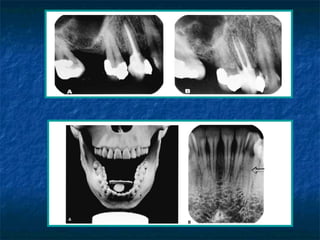

Limitaciones de las radiografías.

   2 dimensiones son mostradas.

   Patología pulpar no es distinguible Rx.

   Patología pulpar no se diagnóstica Rx.

   Lesiones en médula son indistinguibles Rx a

excepción de que involucre hueso cortical.

La imagen radio lucida representativa

de la cavidad pulpar indicara si el diente

es potador de uno o más conductos en

función de:

•Centralización, la imagen radiolucida

del canal central.

•La imagen radiolucida y proporcional

en relación al diámetro mesiodistal de

la raíz.

•La imagen del conducto se va

estrechando           uniforme           y

progresivamente en dirección al ápice.

•La imagen del conducto es visible en

toda la extensión de la raíz.

•Líneas    radiolucidas    longitudinales

dispuestas lateralmente a la raíz.

•Imagen radiográfica de dos o más

ápices radiculares.